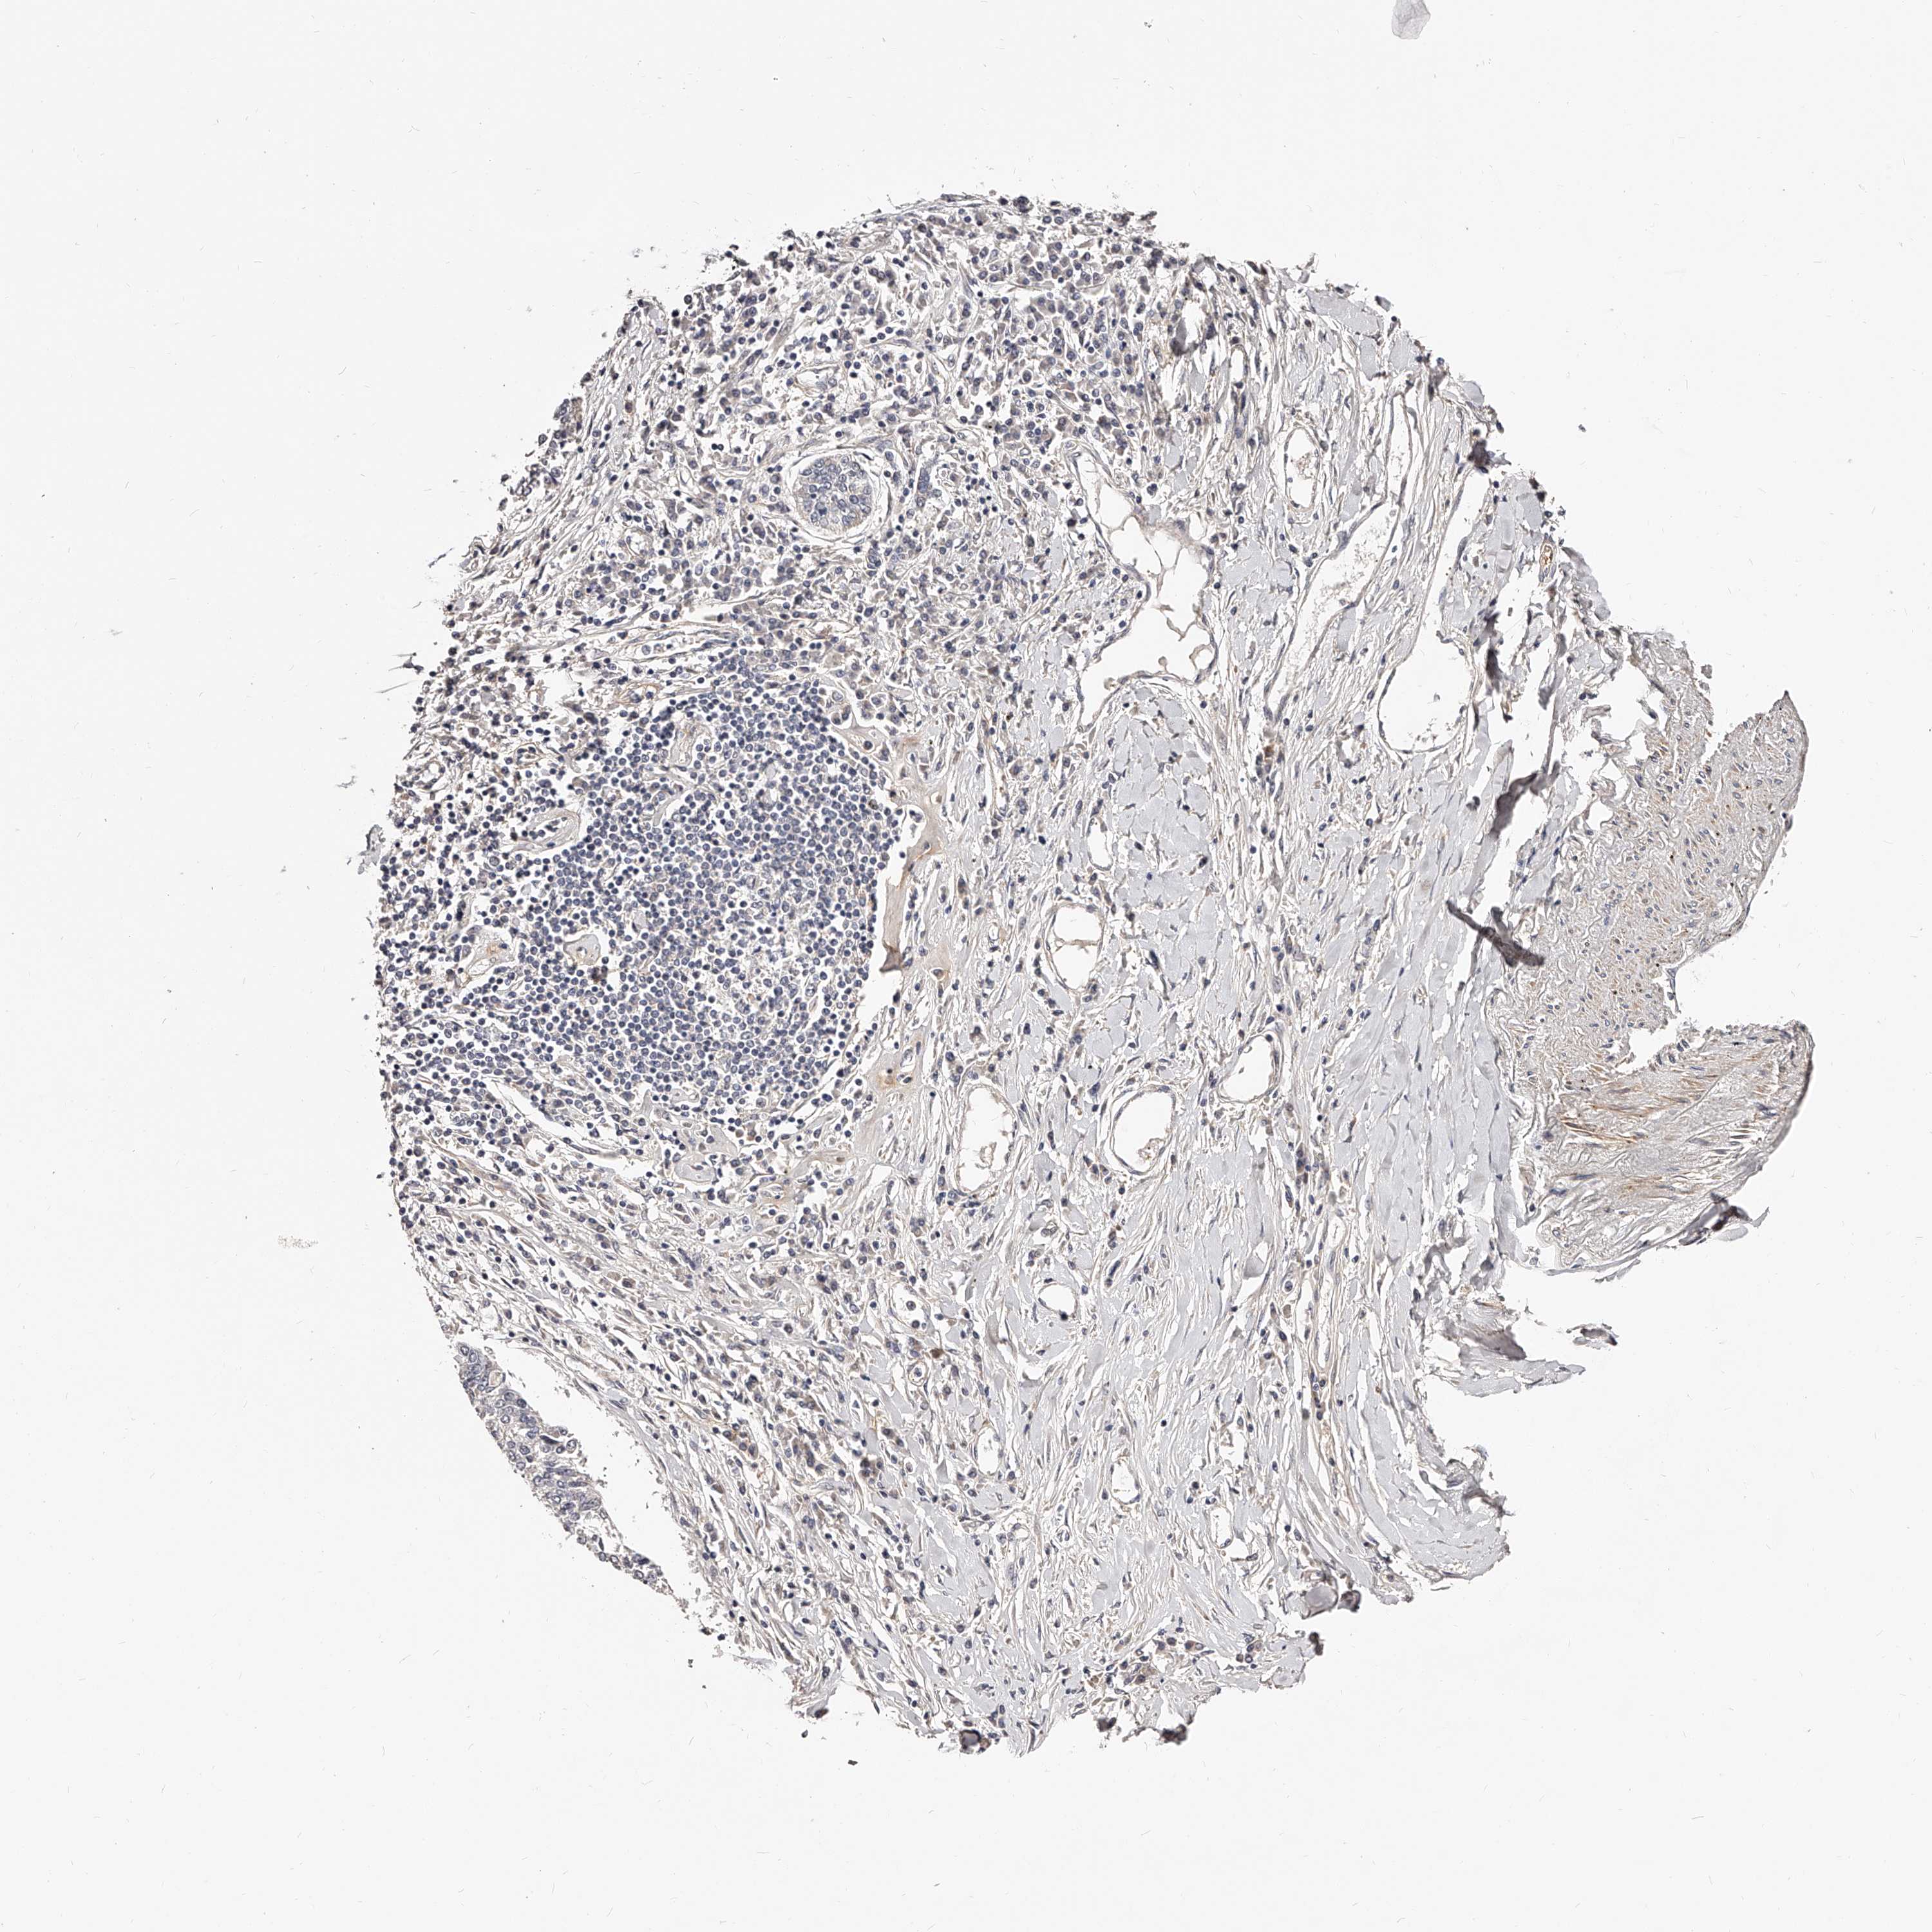

LUNG SQUAMOUS CELL CARCINOMA (TCGA) - Interactive survival scatter ploti

The Survival Scatter plot shows the clinical status (i.e. dead or alive) for all individuals in the patient cohort, based on the same data that underlies the corresponding Kaplan-Meier plots. Patients that are alive at last time for follow-up are shown in blue and patients who have died during the study are shown in red.

The x-axis shows the expression levels (FPKM) of the investigated gene in the tumor tissue at the time of diagnosis. The y-axis shows the follow-up time after diagnosis (years). Both axes are complimented with kernel density curves demonstrating the data density over the axes. The top density plot shows the expression levels (FPKM) distribution among dead (red) and alive patients (blue). The right density plot shows the data density of the survived years of dead patients with high and low expression levels respectively, stratified using the cutoff indicated by the vertical dashed line through the Survival Scatter plot. This cutoff is automatically defined based on the FPKM cutoff that minimizes the p-score. The cutoff can be changed by dragging the vertical line or by entering a cutoff value in the square labeled "Current cut-off".

Under the Survival Scatter plot the p-score landscape (black curve; left axis) is shown together with dead median separation (red curve; right axis). Dead median separation is the difference in median mRNA expression between patients who have died with high and low expression, respectively. It is calculated as follows: median FPKM expression of dead patients with high expression - median FPKM expression of dead patients with low expression. This is intended to aid the user in visually exploring custom cutoffs and the associated p-scores and dead median separation.

Individual patient data is displayed and can be filtered by clicking on one or more of the category buttons on the top of the page. Categories describing expression level and patient information include: high, low, alive, dead, female, male and tumor stages. The scale of the x-axis can be toggled between linear and log-scale by clicking on the "x log" button. Mouse-over function shows TCGA ID, patient information and mRNA expression (FPKM) for each patient.

& Survival analysisi

Kaplan-Meier plots summarize results from analysis of correlation between mRNA expression level and patient survival. Patients were divided based on level of expression into one of the two groups "low" (under cut off) or "high" (over cut off). X-axis shows time for survival (years) and y-axis shows the probability of survival, where 1.0 corresponds to 100 percent.

ZNF502 is not prognostic in Lung Squamous Cell Carcinoma (TCGA)

Best expression cut offi

Based on the FPKM value of each gene, patients were classified into two groups and association between prognosis (survival) and gene expression (FPKM) was examined. The best expression cut-off refers the FPKM value that yields maximal difference with regard to survival between the two groups at the lowest log-rank P-value. Best expression cut-off was selected based on survival analysis .

When clicking on this number, the vertical dashed line indicating cut-off, the interactive survival plot, and the Kaplan-Meier curve will be adjusted to show results based on the best expression cut-off.

: 1.48

P scorei

Log-rank P value for Kaplan-Meier plot showing results from analysis of correlation between mRNA expression level and patient survival.

N/A

TCGA RNA samplesi

RNA-seq data is reported as average FPKM (number Fragments Per Kilobase of exon per Million reads), generated by the The Cancer Genome Atlas (TCGA) .

Normal distribution across the dataset is visualized with box plots, shown as median and 25th and 75th percentiles. Points are displayed as outliers if they are above or below 1.5 times the interquartile range. FPKM values of the individual samples are presented next to the box plot.

Average pTPM 1.0

Number of samples 489